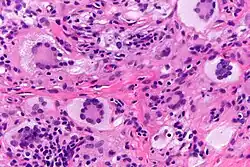

Touton giant cells are named for Karl Touton, a German botanist and dermatologist.[3] Karl Touton first observed these cells in 1885 and named them "xanthelasmatic giant cells", a name which has since fallen out of favor.[4] Karl Touton observed these giant cells when examining a biopsy or skin tissue sample from someone with a lesion under a microscope. He then classified and named these cells due to their strikingly unique appearance. Touton giant cells are still observed using these methods as well as staining with histological dyes such as hematoxylin and eosin (H&E).[5]

Touton giant cells, being multinucleated giant cells, can be distinguished by the presence of several nuclei in a distinct pattern. This pattern is described as a ring-like or wreath-like in the center of a cell. These cells contain a ring of nuclei surrounding a central homogeneous cytoplasm, while foamy cytoplasm surrounds the nuclei.[6][7] The cytoplasm is usually lipid-rich and has a foamy appearance. The cytoplasm is divided into two distic areas: the peripheral zone and the central zone. The central zone is the cytoplasm surrounded by the nuclei which is described as both amphophilic and eosinophilic. Meanwhile, the cytoplasm near the periphery of the cell, the peripheral zone, is pale and contains vacuoles due to the lipid content in this zone of the cell.[1][8]